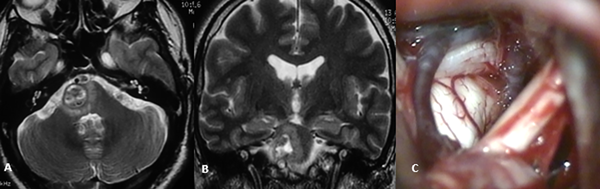

En resonancia magnética (RM) cerebral podemos observar lesiones heterogéneas con intensidades variables en su interior, con zonas hiperintensas secundarias a la metahemoglobina, y un halo hipointenso periférico relacionados con la presencia de hemosiderina. La clasificación por imágenes de Zabramski permite correlacionar los hallazgos en resonancia con el estadio de la enfermedad, desde un tipo I en una hemorragia subaguda, tipo II con hemorragias y trombosis intralesionales en distintas fases de degradación (popcorn sign) hasta una fase III con hemorragia crónica, y un tipo IV relacionada con cavernomas pequeños y telangiectasias. De igual forma, la RM permite valorar la localización detallada de la lesión y su relación con la superficie pial o ventricular, aspecto de importancia en la determinación de la vía de acceso (Figura 1).1,7,11

Figura 1: RM ponderación en T2, proyección coronal (A) y sagital (B) donde se evidencia cavernoma Zabramski II localizado a nivel del bulbo raquídeo. Imagen intraoperatoria de mismo paciente (C) con evidencia de lesión en contacto con superficie pial del tronco cerebral.